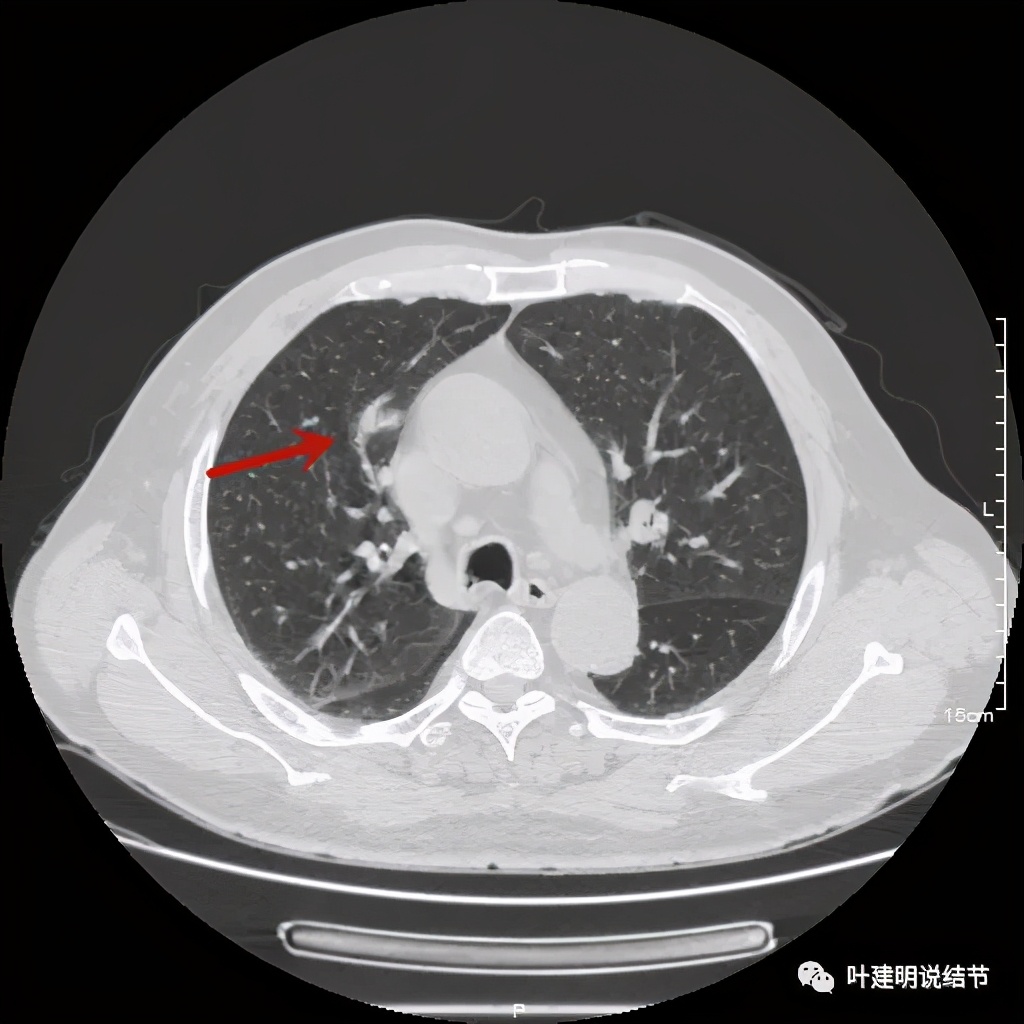

金华的某A,男性,70岁,因检查发现右上肺占位入院,没有临床症状,肿瘤筛查指标正常,血常规与CRP正常。胸部CT检查报告考虑恶性可能:

直径约2.4厘米,密度欠均,血管贴边,增强轻度强化。单从描述看,恶性可能性较大。我们再来看看图像:

可见右上叶占位,我们现在知道了结果以后回头看,发现病灶的边缘在各个层面都是过于光滑(绿色箭头所示)。血管紧贴病灶边走行(桔色箭头所指),是不是有侵犯看不清楚,若是靶扫描加重建可能会更清楚点。支气管感觉也是贴着病灶走,但有的层面是不是截断,也不看的不太清楚。有的层面见局部有点状高密度(蓝色箭头所指),是不是错构瘤的局部钙化呢?若是纵隔窗又是如何?

上图示病灶